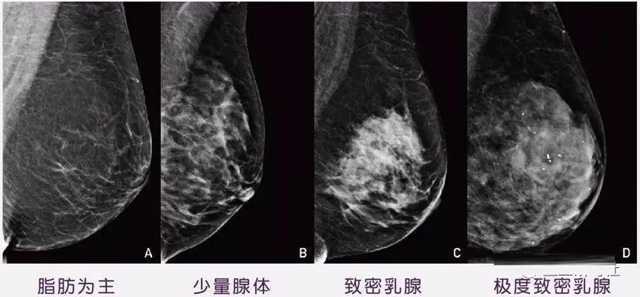

女性乳腺的自我檢查,特別是注意有小結(jié)節(jié),腫塊,乳頭有液體滲出情況,需要通過乳腺DR,X光線,磁共振等影像技術(shù)檢查。胸的大小跟乳腺癌沒多大關(guān)系,乳腺的密度大發(fā)病率高一些,胸小脂肪少致密性大。更容易乳腺癌。這個還不能通過自我檢查來確認(rèn)。致密乳腺組織看上去是白色或淺灰色需要通過乳腺X射線檢查。

乳腺X射線有輻射,40歲以下的女性沒有高危因素跟臨床特征,醫(yī)生都是不建議使用鉬靶檢查。乳腺超聲無創(chuàng)無輻射,對乳腺組織分辨率高。可以將乳腺腫塊從致密型乳腺組織中輕松查出來,多普勒模式檢查乳腺及病變,超聲小于1厘米的病灶非腫塊性乳腺癌檢出率低。超聲檢查結(jié)果依賴醫(yī)生水平和經(jīng)驗(yàn),乳腺DR超聲推動乳腺超聲圖像的標(biāo)準(zhǔn)化,提高檢查的準(zhǔn)確率。對乳腺組織內(nèi)的細(xì)小鈣化灶, 從范圍、乳腺X射線形態(tài)以及分布特點(diǎn)上進(jìn)行定性診斷。造影劑增強(qiáng)型乳腺X線攝影靜脈注射碘化造影劑結(jié)合乳房X線攝影。磁共振MRI對乳腺癌研究的深入對軟組織具有較高的分辨率等特點(diǎn),在臨床上被廣泛認(rèn)可。乳腺CT的探測器圍繞著乳房成像,無痛無擠壓,3D乳房圖像乳腺病灶的大小、數(shù)量、形狀、位置以及血管分布。一次掃描可創(chuàng)建多達(dá)兩千張投影圖像 。乳腺PET,適合普通人群和乳腺癌高危人群早期檢測,發(fā)現(xiàn)極早期微小病灶并明確定性。